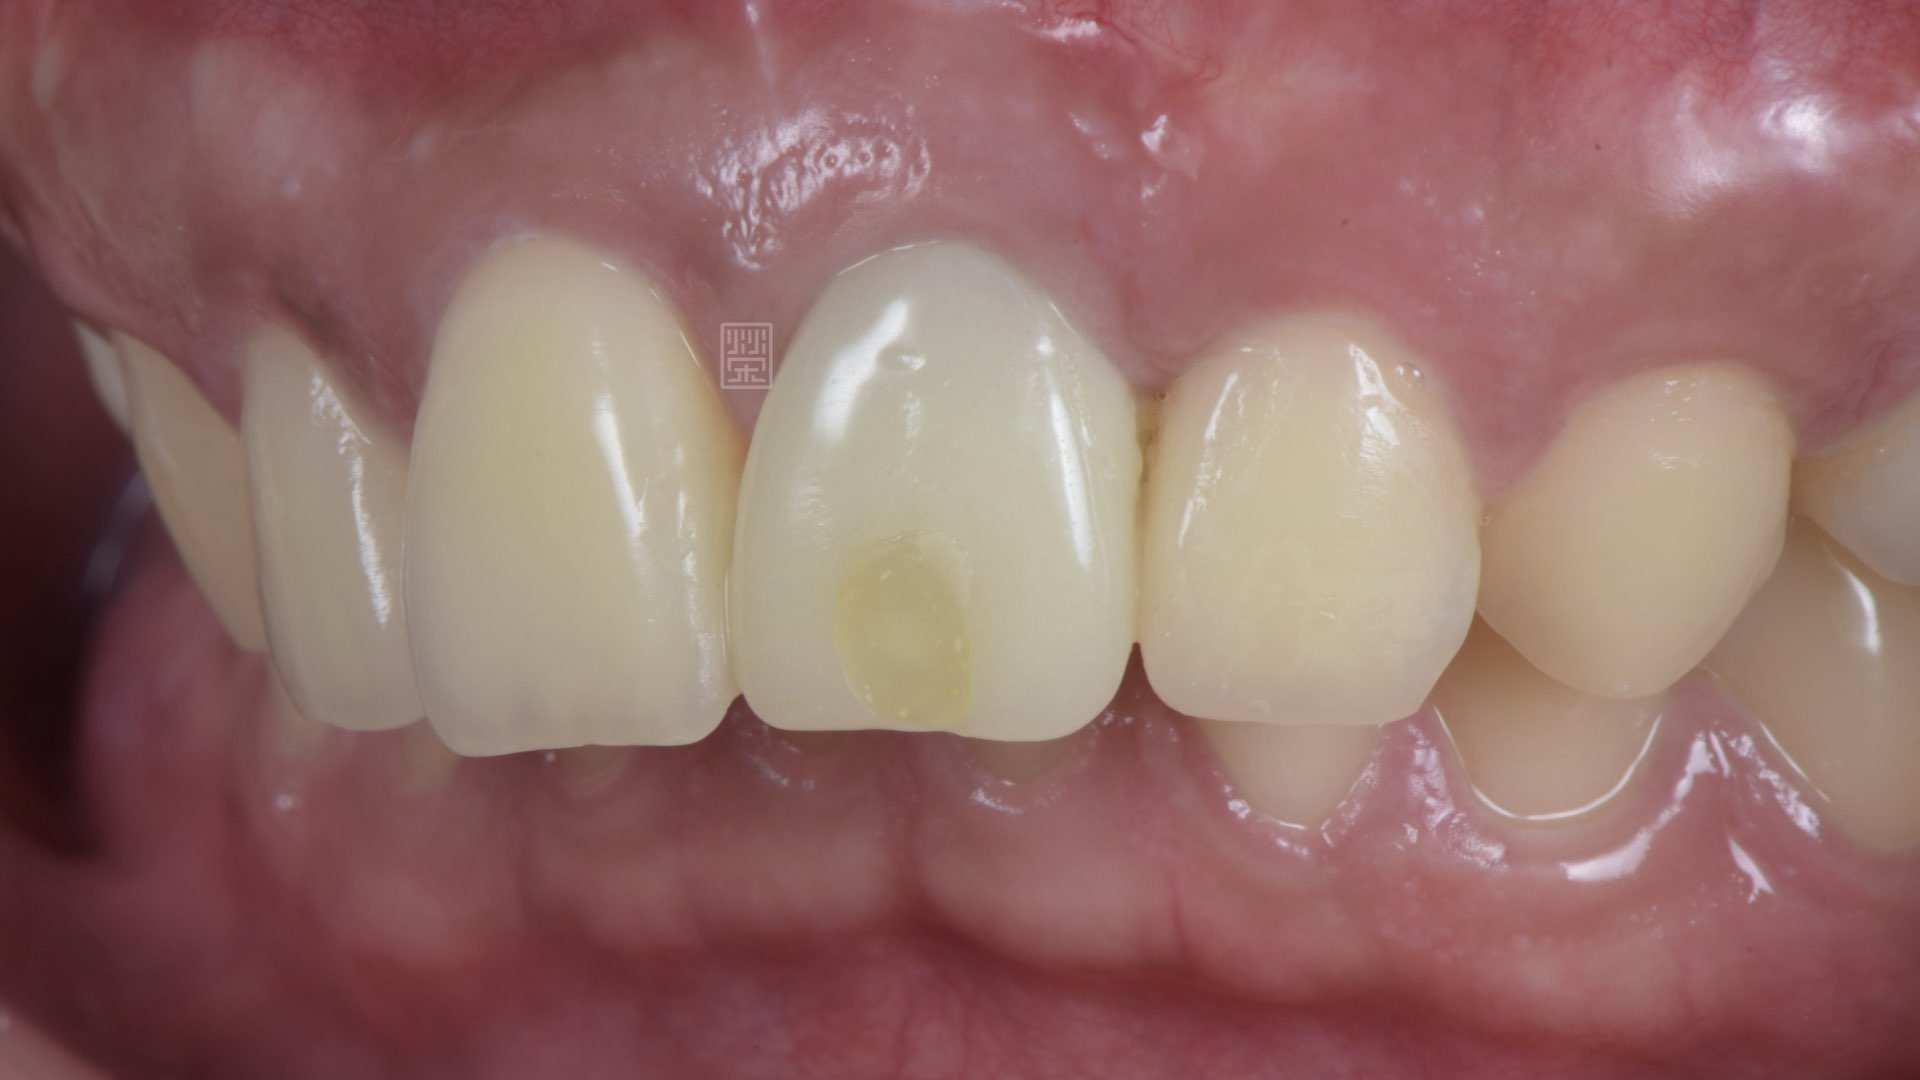

植牙完成